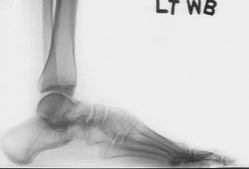

Diagnosis: Right planovalgus foot

History: 15 + 2 y/o female who underwent a R calcaneal lengthening (6/95), L calcaneal lengthening and TAL (1/96) and is now returning without having resumed full activity and is concerned with the marked planovalgus deformity of the right foot.

Pre-op radiographs